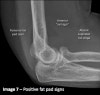

Anterior fat pad sign : 70-80% Intra-articular fracture

Posterior fat pad sign : 90% Intra-articular fracture.

The anterior fat pad can be displaced up and out by fluid in the elbow joint, creating the "sail sign". This usually indicates a fracture in children in the setting of an injury.

Fluid in the elbow joint can displace the fat pad up and out making it visible on the lateral view.

Indicates that the patient has sustained an intra-articular injury. Importantly, it does not indicate that the patient has definitely sustained an intra-articular bony injury.